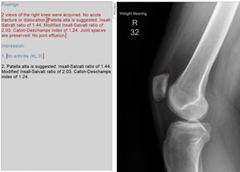

Knee Patella Malalignment

Knee Patella Malalignment AI

Automatic Diagnosis on X-ray. Measurement of Install-Salvati, Caton-Deschamps.

Aryan Kaul, Jason Pai, et al.